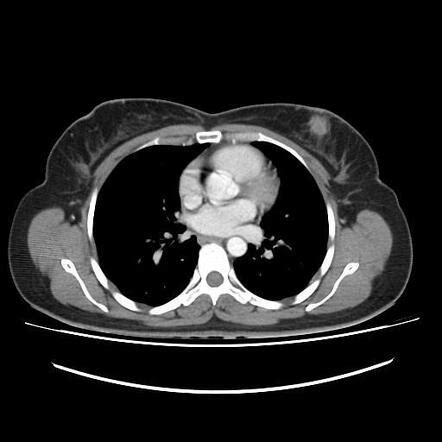

Guys, let’s talk about the diagnostic process for metastatic triple-negative breast cancer (mTNBC) . When your doctor suspects that your breast cancer might have spread, or if you’re presenting with symptoms that point towards metastasis, a series of tests will be initiated. It’s not just one single test; it’s a whole investigative journey to get a clear picture. First off, they’ll likely start with a physical examination and ask detailed questions about your symptoms and medical history. Then come the imaging studies . These are super important for visualizing what’s going on inside your body. You might undergo a CT scan (Computed Tomography), which uses X-rays to create detailed cross-sectional images of your body. This can help detect tumors in organs like the lungs, liver, or adrenal glands. A bone scan is specifically designed to check if the cancer has spread to your bones. You’ll be injected with a small amount of radioactive material that attaches to areas of bone activity, and a special camera will detect where this material has gathered, highlighting potential metastatic sites. A PET scan (Positron Emission Tomography) is another powerful tool. It uses a radioactive tracer that your body absorbs, and cancer cells tend to absorb more of this tracer, making them light up on the scan. PET scans can help identify cancer throughout the body. An MRI (Magnetic Resonance Imaging) might be used, especially if brain or bone involvement is suspected, as it provides very detailed images of soft tissues and bones. If these scans show suspicious areas, the next crucial step is a biopsy . This is the definitive way to confirm cancer and its type. A small sample of tissue is taken from the suspected metastatic site (e.g., a nodule in the lung, a lesion in the liver or bone). This sample is then sent to a lab for analysis. Pathologists will examine the cells under a microscope and perform crucial tests to determine if the cancer cells are indeed from the breast and, critically, if they are triple-negative (negative for ER, PR, and HER2). Sometimes, a biopsy of the original breast tumor might be redone or reviewed to ensure the triple-negative status is accurate. In some cases, liquid biopsies – analyzing cancer DNA shed into the blood – are becoming more common and can provide insights into the cancer’s genetic makeup and mutations, which might guide treatment decisions. Genetic counseling and testing may also be recommended, especially if there’s a family history of breast or ovarian cancer or if BRCA mutations are suspected, as these can impact treatment options and family planning. It’s a thorough process, and while it can feel overwhelming, remember that each step is designed to gather the vital information needed to fight this disease effectively. It’s all about getting the right information to the right people to make the best treatment choices.